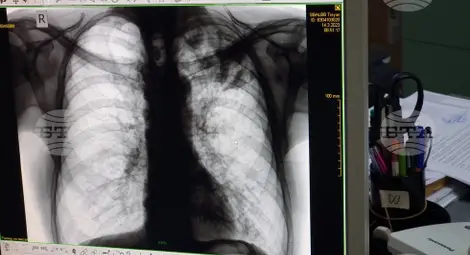

Безплатни прегледи за туберкулоза ще се извършват в областната болница в Ямбол

По данни на Регионалната здравна инспекция през 2024 г. в област Ямбол са регистрирани 19 случая на туберкулозна инфекция, а през предходната 2023 г. заболелите са били 23-ма.

През 2024 г. заболеваемостта у нас е 13,7 на 100 000 население, като са регистрирани 913 случая. За сравнение, през 2014 г. техният брой е 1872, като се запазва тенденцията броят на мъжете да е по-голям от този на жените.